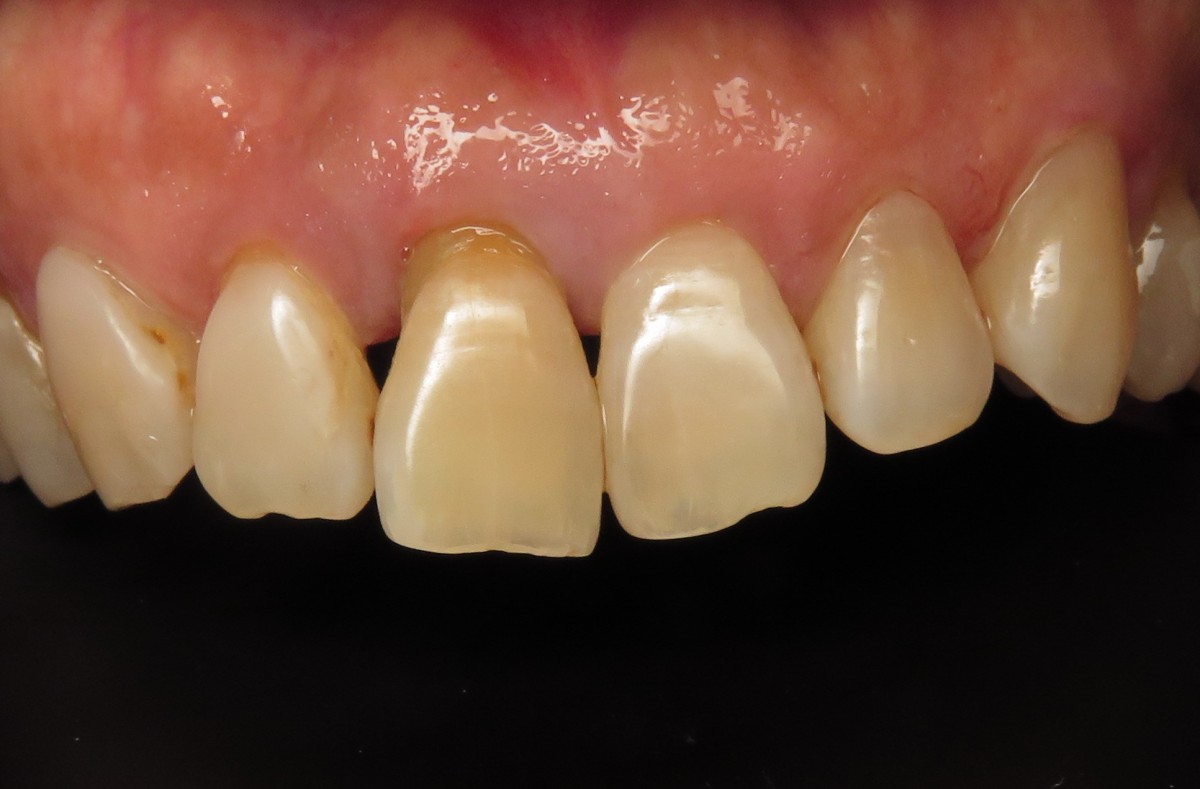

Four months after implant placement the patient returned for evaluation of the implant and final prosthetic procedures. Clinically the soft tissues looked healthy and pink, despite the poor oral hygiene (Figure 7). Bone levels were also stable and improved since placement. RFA measurements were at 69 bucco-lingually and 66 mesio-distally, showing an increase since placement. A closed tray impression coping was used to capture the position of the implant and surrounding structures. To fabricate the final restoration, a prefabricated zirconia abutment was used with 15-degree angle correction (Figure 9). The lab modified the abutment as needed and fabricated a cement retained final layered zirconia crown. Caution was taken to minimize excess cement (Figure 10) and deliver a well-fitting all-ceramic restoration over a ceramic implant (Figure 11).